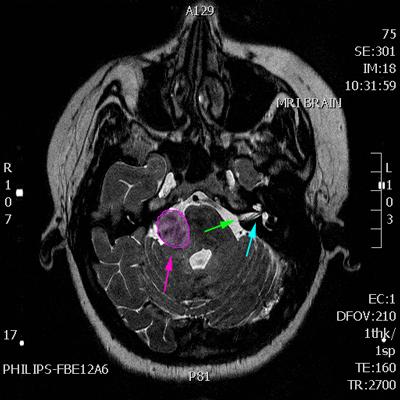

Αιθουσαίο σβάννωμα αριστερά (κόκκινο περίγραμμα). Φυσιολογικός έσω ακουστικός πόρος δεξιά (πράσινο βέλος), ακουστικό όργανο (κοχλίας) και όργανο ισορροπίας (λαβύρινθος) με κυανό βέλος. |